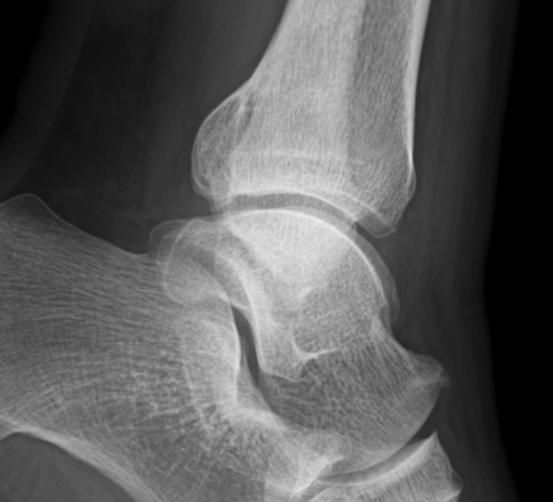

최근 발목이 아파 병원에 방문했더니 발목 관절염 초기라고 이야기해서

엑스레이 확인 후 자료 받아와 확인 해봤는데 저는 잘모르겠어서....ㅠㅠㅠ

병원 3군데 갔는데 2군데는 맞다 한군데는 애매하다는 소견을 내려주셨습니다.

혹시 엑스레이 사진상 발목 관절염이 확인 되는지 질의 드립니다.

만약 확인 되면 발목 관절염 현재 몇단계 정도 진행중인가요?

• 3번 째 사진

엑스레이상에서는 양쪽의 비교를 해보시는 것이 가장 정확하지만, 여러 의견을 들으신 것처럼 발목관절염의 초기로 보이지만, 관절에는 큰 변화가 없는 것으로 보이는데요

• 안녕하세요. 남희성 의사입니다.

애매하다고 표현하신 경우에도 다른 의사들이 관절염이 있다고 이야기하셔서 애매하다고 표현하셨지 골관절염이 아니라고 판단하셨을겁니다.

제가 보기에는 관절염 소견이 보이지 않습니다.

만약에 관절염이 맞다고 하더라도 가장 초기단계로 생각하시면 되겠습니다.